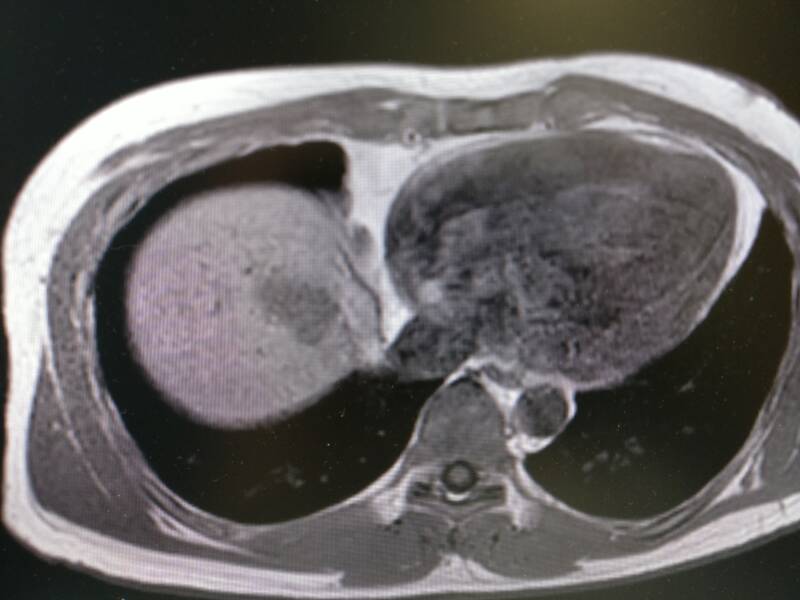

Het plaatje hierboven is een MRI-scan. Hierop kun je de weefsels veel duidelijker zien. Deze MRI is ongeveer dezelfde locatie als de twee bovenstaande plaatjes. Je ziet weer rechts het hart en links de lever. Mijn tumor ziet er nu donkergrijs uit in het lichtere grijs van de lever. In tegenstelling tot een CT-scan, waar die botten wit oplichten, zie je de botstructuur veel minder duidelijk op een MRI. Maar de spieren en de vetlagen onder mijn huid die op de MRI mooi zichtbaar zijn, zijn een grijze brij op de CT.

Als laatste nog twee plaatjes van de MRI scan. Hierop zie je de stappen waarmee de artsen door mijn lichaam kunnen scrollen. We gaan van boven naar onderen. Mijn lever wordt dus steeds groter op de plaatjes omdat die onderin mijn lichaam groter is.